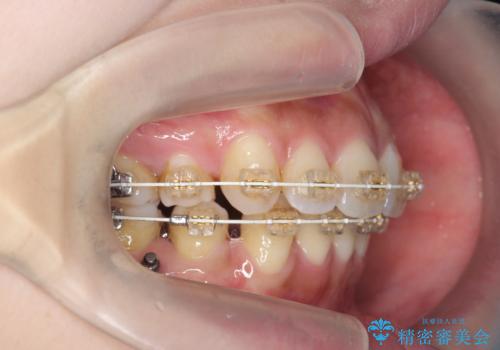

[ 受け口傾向のマウスピース矯正 ] マイクロインプラントで行う確実な後方移動

- 前歯のがたつきや、奥歯の噛み合わせの改善を求めて来院されました。

検査を行った結果、受け口の傾向(下顎前突)の改善が必要であることがわかりました。

マウスピース矯正のトップブランドである、インビザライン矯正システムを用いるとともに、マイクロインプラントを併用することで下顎の奥歯後方移動することで前歯のがたつきと奥歯の噛み合わせを合わせて治療していきます。

奥歯の後方移動はマイクロインプラントを用いることで、治療の成功する確率を高めることができます。